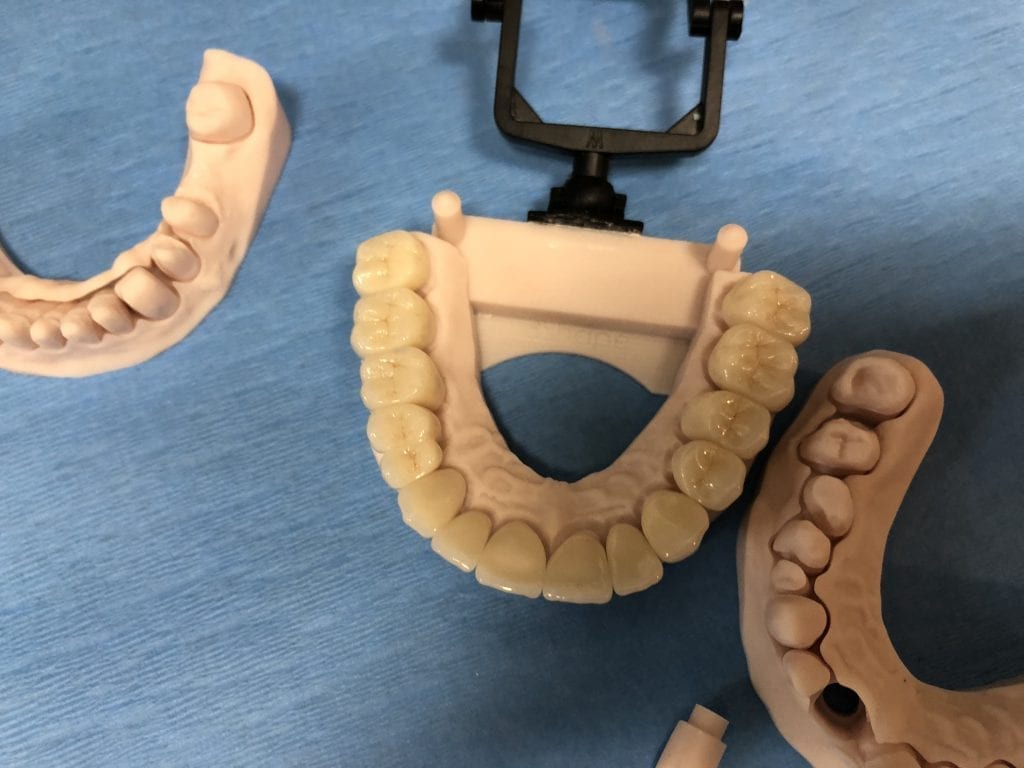

The case was designed by CADENT BESSA, and the models were printed by Burbank Dental Lab with Carbon Printers. There restorations were milled and cut back and layered by Burbank Dental Lab

IMAGES OF PRINTED MODELS